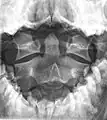

A fracture of the base of the dens as seen on plain X-ray